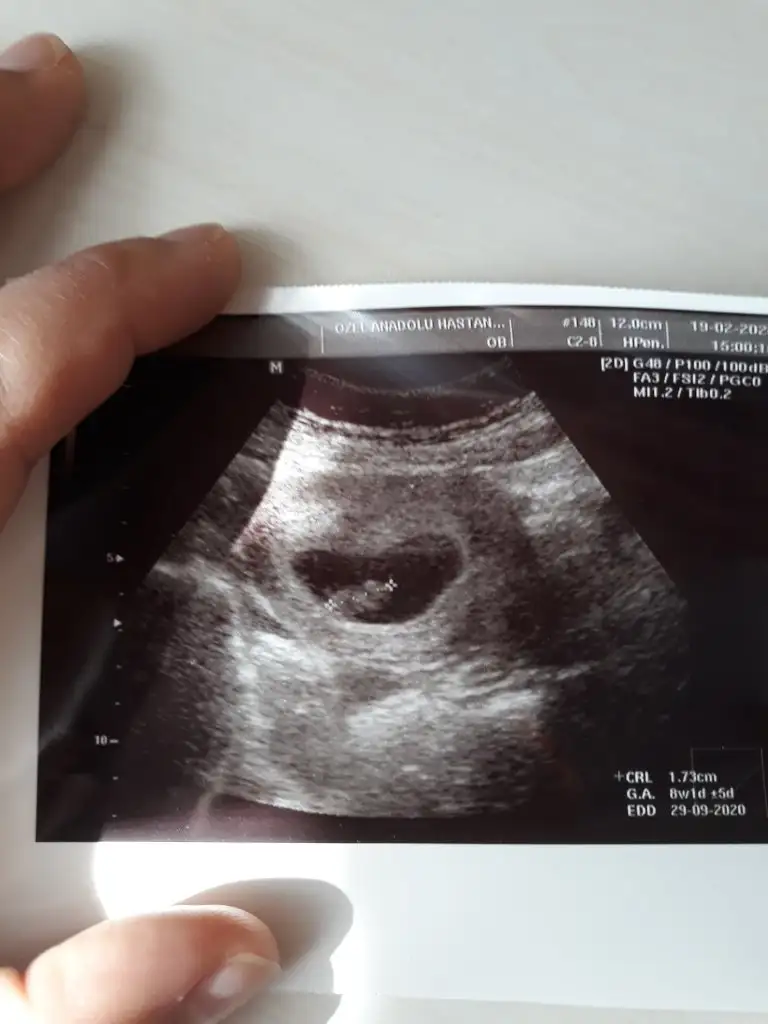

Bunlar da benim ultrason görüntülerim. İlki 6+5. İkincisi 8+1. İkisi de karından ultrason. Cinsiyet tahmini yapabilir misiniz?Yaaa rabbim bu defa saglıkla nasip etsin inşallah. şimdi kaç haftalık hamilesiniz dünkü 7 + olan sizin 6+4 olan arkadaşınızmı o zaman şimdilik ikiside kız görünüyor siz 11 yada 12 hafta paylaşın

Yolk saç solda erkek 6.5 usg de 8+1 de soldaBunlar da benim ultrason görüntülerim. İlki 6+5. İkincisi 8+1. İkisi de karından ultrason. Cinsiyet tahmini yapabilir misiniz?